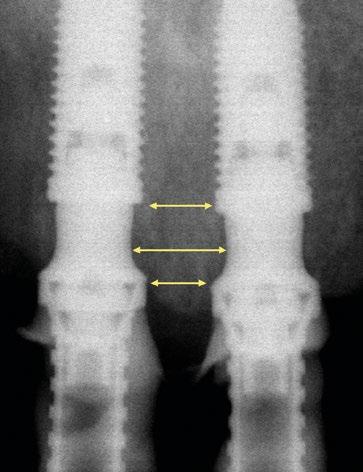

tura de la encía y calcular la angulación del implante con respecto a la emergencia de los dientes para determinar la necesidad de utilizar un pilar angulado. Con la evolución de la implantología, los conceptos de planificación protésicamente guiada, las filosofías de “cero pérdida ósea” (zero bone loss concepts, Linkevicius [Ref.1]) y los conocimientos de la estética actual sobre implantes están presentes a la hora de colocar los implantes y rehabilitarlos. El objetivo ya no es buscar una rehabilitación funcional, sino que también es lograr una apariencia estética natural duradera y estable a lo largo del tiempo evitando problemas como la recesión gingival o la pérdida ósea marginal e interproximal. El nivel de conocimiento que existe en implantología unitaria implica tal cantidad de conceptos y detalles a nivel biológico y protésico que dificulta mucho y hace prácticamente imposible la utilización de los pilares Multi-unit clásicos para situarlos en la zona transgingival y lograr emergencias estéticas adecuadas. Como siempre, Nobel Biocare ha comprendido estas necesidades y se ha adaptado a estos requisitos introduciendo nuevos diseños de perfiles que se adaptan mucho mejor a este tipo de situaciones y resultados. El objetivo de esta publicación es presentar las características de los nuevos pilares Multi-unit y sus finalidades, así como también las indicaciones de su utilización.

La importancia en la preservación del hueso crestal alrededor de los implantes y de las distintas estructuras del fenotipo periimplantario es vital para el mantenimiento y éxito funcional y estético a largo plazo (Ref.2). La utilización de conexiones cónicas robustas, mecánicamente estables y con cambio de plataforma como las de NobelActive® y NobelParallel™ pueden ayudar al mantenimiento del hueso crestal (Ref.3). Sin embargo, también es importante asociar este tipo de conexiones con la posición tridimensional del implante (Ref.4). Concretamente en el plano apico-coronal, la colocación de los implantes en posiciones subcrestales va a ayudar no solo a mantener el hueso, sino que va a permitir generar el espacio necesario para establecer una zona de transición biológica y protésicamente necesaria para desarrollar los perfiles de emergencia adecuados hasta llegar a la anatomía del margen gingival de la corona o perfil crítico (Ref. 5). Según las publicaciones, este espacio está establecido 3,5-4mm del margen gingival (Ref.6, Ref.7). Desde el punto de vista restaurador en implantes unitarios, es conocido que estos perfiles de emergencia deben ser diseñados con una transición suave. Partiendo desde un diámetro estrecho que progresivamente se va ensanchando. Siempre que el implante esté bien colocado tridimensionalmente el resultado será un perfil de emergencia cóncavo en el área subgingival. (Refs.8,9,10). La finalidad del concepto es proporcionar el máximo espacio horizontal para el crecimiento de tejido conectivo supracrestal alrededor de la interfase de titanio o pilar personalizado ofreciendo protección al implante a costa de maximizar el grosor y estabilidad a las estructuras del fenotipo periimplantario (Ref.11).

El verdadero reto surge en situaciones en las que es posible crear una prótesis múltiple del tipo FP1 (Ref.12), donde siempre se debe utilizar un pilar Multi-unit. Cuando se utiliza un implante asociado a este tipo de pilar para crear una emergencia natural desde la encía, éste se debe planificar teniendo en

cuenta que el volumen del pilar va a ocupar prácticamente toda el área de la altura de tejido supracrestal (“Suprecrestal tissue height” Ref. 11) y debe estar “camuflado” en dicha zona de transición ocupando gran parte del espacio para el tejido conectivo supracrestal y del perfil de emergencia de la restauración (Ref. 13). Ya sea un pilar recto o angulado, debido a sus formas robustas y perfiles anchos, resulta difícil de planificar su colocación en zonas estéticas ya que el complejo implante-pilar se va a comportar como un implante tipo “tissue level” (Ref.14)

(Fig.1). Con los diseños clásicos de pilares no se van a poder respetar las concavidades subgingivales deseadas y siempre va a implicar la eliminación de hueso, sobre todo a nivel interproximal y vestibular en la zona del cenit del diente (Ref.15) (Fig.2). Las consecuencias automáticas serán picos de hueso interproximales reducidos, papilas más cortas y dientes con cenits más planos y anchos en el tercio gingival. Incluso en situaciones de implantes adyacentes puede provocar la pérdida o ausencia total de papila interimplantaria (Ref.7) (Fig.3).

Con respecto al Multi-unit recto, su principal característica es la emergencia desde la plataforma del implante con un perfil completamente cóncavo. Por una parte, va a maximizar el efecto de “cambio de plataforma” en su parte más crestal a nivel de la plataforma del implante y por otra va a facilitar mucho más espacio para la creación de tejido conectivo supracrestal a lo largo de toda la transición hasta la plataforma restauradora. El perfil cóncavo del pilar también respetará en mayor medida los espacios comprendidos entre el pilar y el hueso interproximal (en el caso de una colocación subcrestal entre 1,5 y 2mm) para poder preservar al máximo las estructuras anatómicas presentes que soportarán las papilas periimplantarias.

Así como el diseño clásico de pilar hacía prácticamente imposible la colocación de implantes inmediatos en zona estética, el nuevo perfil cóncavo del pilar Multi-unit hace que se convierta en un pilar ideal para estas situaciones. La altura de pilar de 3 ,5 mm, hace que se pueda colocar la plataforma del implante en la posición corono-apical deseada con respecto al margen gingival sin involucrar el hueso adyacente y permitiendo desarrollar un mínimo perfil de emergencia restaurador más horizontal para soportar cenit y tejido interproximal. (Fig.6-7) Otra característica de diseño importante es la reducción del bisel de la plataforma res-

tauradora tanto en los pilares rectos como en los pilares angulados. Sin cambiar su diámetro clásico de 4,8mm ni su compatibilidad para atornillar y asentar cualquier aditamento restaurador de toda la gama Multi-unit, el nuevo pilar presenta una plataforma mucho más fina y estilizada que facilitará también su inserción incluso sin necesidad de utilizar la fresa “bone mill” o molinillo de hueso. De esta manera no solo se seguirá incrementando la preservación ósea, sino que también se reducirán los tiempos quirúrgicos al evitar tener que atornillar y desatornillar la guía del molinillo o “Bone Mill Guide”. (Figs. 8-12)

La colocación del implante inclinado de 30º siempre implica que la zona más mesial de la plataforma se encuentra en posición yuxtaósea y la zona distal en posición subcrestal. Clásicamente se debe utilizar el instrumento “bone mill” de 5,2mm (NP) o 6,2mm (RP) para poder insertar el pilar en la posición deseada. En la figura 14 (Fig.14) se observa una situación clínica comparativa donde se han colocado implantes inclinados con una orientación de 30º aproximadamente en dirección hacia los rebordes piriformes en una premaxila. Claramente se puede observar la cantidad de remodelación ósea provocada por el molinillo versus la preservación que ofrece la colocación el nuevo Multi-unit sin necesidad de acondicionar la cresta ósea. En configuraciones de tipo All-on-4®, en los implantes distales se produce una situación similar. El inconveniente que se puede producir en estos casos es la posibilidad de la aparición de una recesión de la mucosa periimplantaria alrededor del pilar precisamente por la combinación de quedar la zona sin soporte óseo y por el propio volumen excesivo que ocupa el pilar. Por el contrario, mediante la utilización de los nuevos perfiles no existe necesidad de remodelar el reborde alveolar y conjuntamente al menor volumen que ocupan los pilares, el tejido (si es suficiente) será capaz de mantenerse en mayor medida. En las figuras 15 a 18 (Fig.15-18) se describe una situación común donde se utiliza el pilar Multi-unit de 17º. En pacientes edéntulos o futuramente edéntulos en la zona de la premaxila. Para maximizar el hueso disponible en esta

za un pilar de 3,5mm de altura, existe el riesgo de reducir el espacio protésico y de nuevo que aparezca una recesión gingival si el implante se coloca a nivel crestal o ligeramente subcrestal (1-1,5mm). Independientemente de la altura seleccionada (2,5mm o 3,5mm), de nuevo, esta situación implica la remodelación ósea mediante bone mill para acomodar el pilar. En la Fig.10 se observa cómo queda la remodelación

circular en el implante en posición #1.2 versus la no remodelación de un pilar de nuevo perfil de altura 3,5mm en un implante colocado 2mm subcrestal. La limitación de los pilares de 17º clásicos es que emergen muy rápidamente hacia el diámetro de 4,8mm de la plataforma restauradora y de nuevo no existe espacio suficiente para el establecimiento biológico de la altura de tejido supracrestal. Claramente se observa en las

radiografías periapicales comparativas a los 3 meses de la colocación como el implante en posición #1.2 tiene signos de remodelación fisiológica. Hecho que no ocurre en los pilares con nuevos perfiles al ofrecer transiciones más suaves que respetan los principios biológicos.